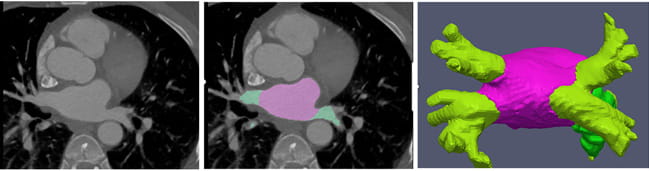

Pretreatment mapping of the left atrium is much quicker with the help of AI. The images show a standard heart CT scan (left), a scan with AI mapping (middle), and a detailed AI map of the left atrium (right).

Normally, patients about to undergo catheter ablation are sent to the radiologist for a computed tomography (CT) scan or a magnetic resonance image (MRI). The radiologist then processes the image to give a detailed map of the left atrium and the pulmonary veins back to the electrophysiologist. This process can normally be completed in 10 to 15 minutes. However, Burt and his team have developed an artificial intelligence algorithm that can provide a detailed map of the left atrium with 95% accuracy in just 10 seconds.